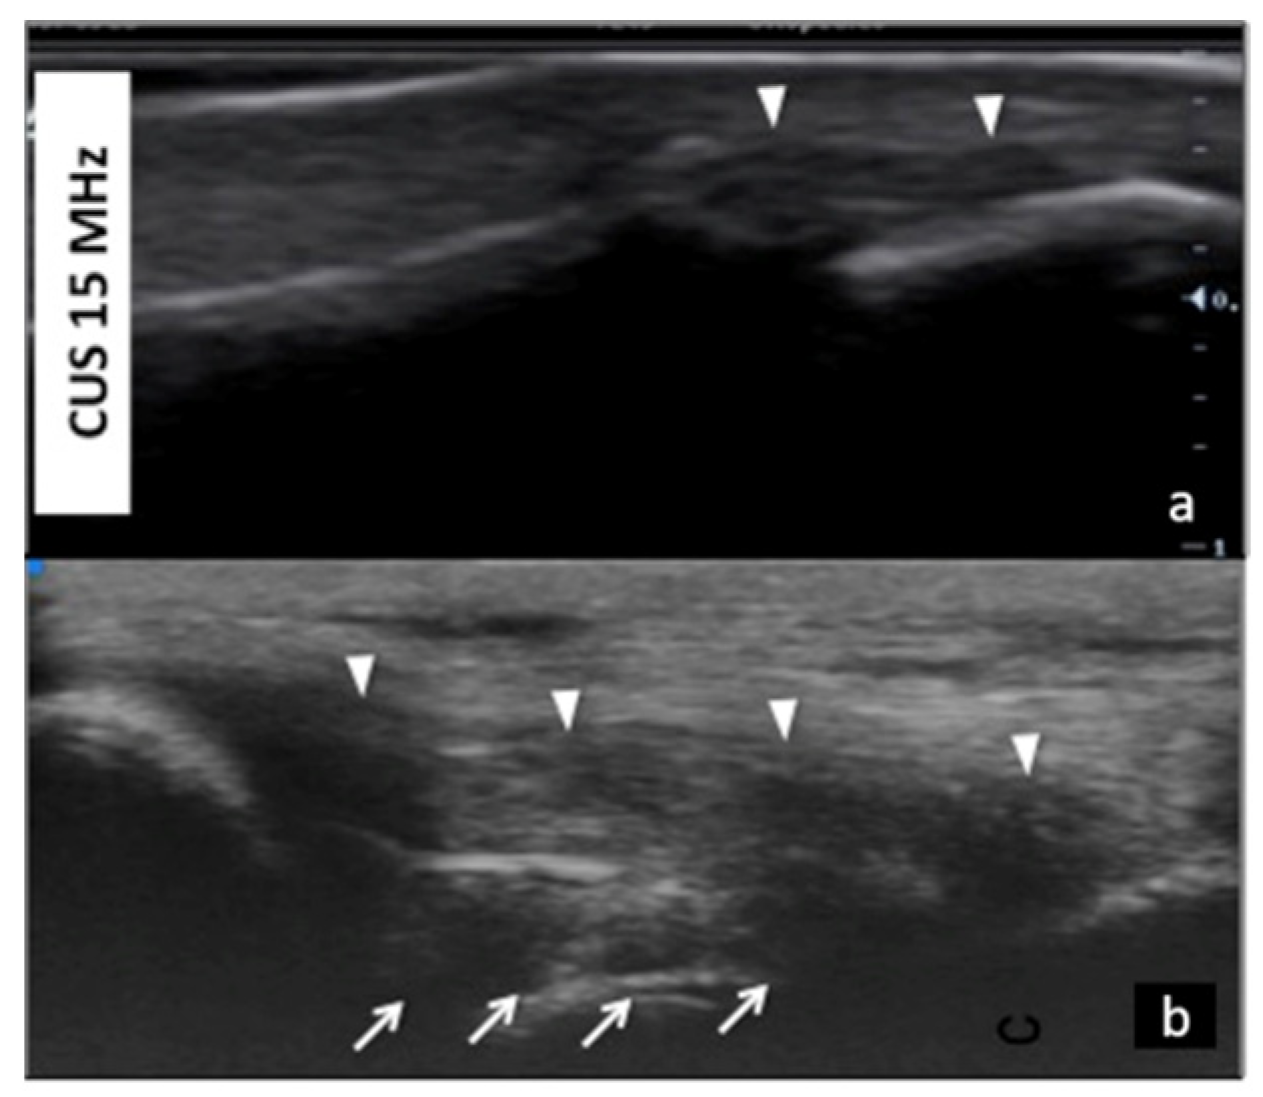

UHFUS offers a detailed and magnified representation of collateral ligaments of the hand (Figure 6).

Figure 6.

Collateral ligaments of interphalangeal joints: comparison between 50 MHz probes in (a) and 15 MHz CUS (arrowheads) in (b). In (a), UHFUS gives a more detailed and magnified representation of both deep (white arrows) and superficial (white arrowheads) components of the ligament.

This could become useful in demonstrating even partial injuries of these structures. In particular, injury to the ulnar collateral ligament (UCL) complex of the thumb is a common traumatic lesion that requires prompt imaging evaluation for adequate treatment. UHFUS could have a key role in the illustration of both static and dynamic findings related to UCL injuries with even more details than MRI imaging (Figure 7 and Figure 8).